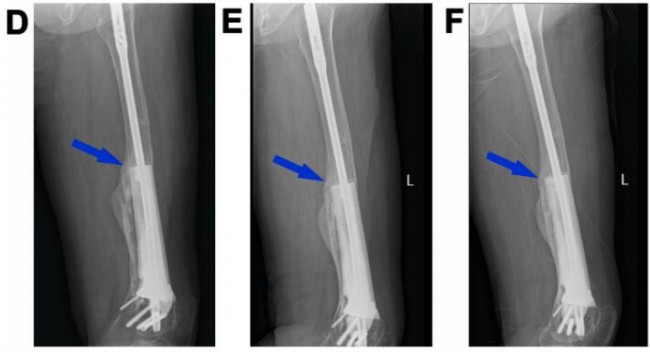

图5.3D打印多孔Ti6Al4V内植物重建股骨缺损(病例2)。末次术后即刻(A)和植入后2(B)、5个月(C)、8个月(D)、14个月(E)和20个月(F)重建的11cm股骨缺损的X线图像。蓝色箭头表示内植物和宿主骨之间的骨整合。